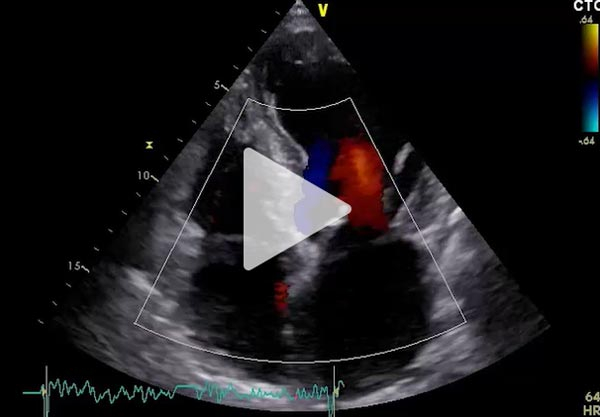

ETT de contrôle après cardioversion à USIC

- VG dilaté ( DTD 65 mm VTD 89 ml/m² ), hypertrophié ( SIV 14 mm PP 11 mm ),

- FEVG 33% en SP, hypokinésie diffuse plus marquée en antérieur et antérolatéral

- Débit cardiaque modérément abaissé

- IM modérée stable, pas de valvulopathie aortique significative

- Cavités droites dilatées normokinétiques

- PAPS 42 mmHg et POD 5mmHg

- Péricarde sec

Vidéo 1